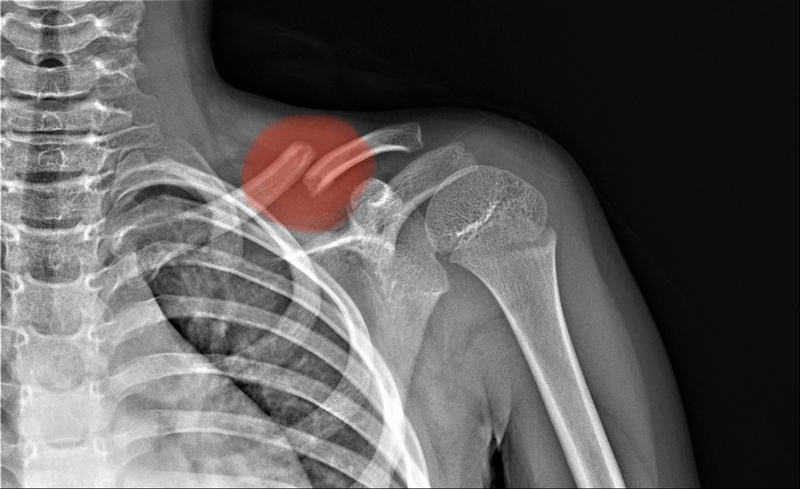

Gãy xương đòn di lệch thường gặp nhất ở người bị chấn thương, té ngã, tai nạn giao thông hoặc tai nạn lao động. Các phương pháp chẩn đoán và điều trị gãy xương đòn di lệch khá giống với các trường hợp gãy xương đòn thông thường nhưng cần lưu ý nhiều điều.

Trước khi đi sâu hơn tìm hiểu về gãy xương đòn di lệch, bạn cũng cần biết gãy xương đòn là gì. Theo giải phẫu, xương đòn hay còn gọi là xương quai xanh là phần xương nằm dưới da, từ trên xuống thì xương đòn là 1 xương khá dài và có hình dáng gần giống với hình chữ S khi có 2 chỗ cong nhẹ ở 1/3 ngoài giáp, 1/3 giữa giáp và 1/3 ở trong. Điểm yếu nhất và dễ bị tác động dẫn đến gãy xương đòn di lệch nhất là 1/3 giữa và 1/3 ngoài của xương đòn.

Tình trạng gãy xương đòn là một dạng chấn thương gãy xương rất phổ biến hiện nay, đa phần là do chấn thương. Tỷ lệ các ca gãy xương đòn chiếm đến 40% tổng số các trường hợp bị gãy xương ở vùng vai và chiếm 2.5 – 6% trong tổng số các trường hợp gãy xương nói chung.